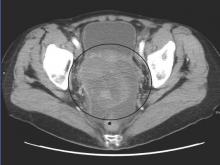

Courtesy Wikimedia Commons/James Heilman, MD/CC-BY-SA-3.0